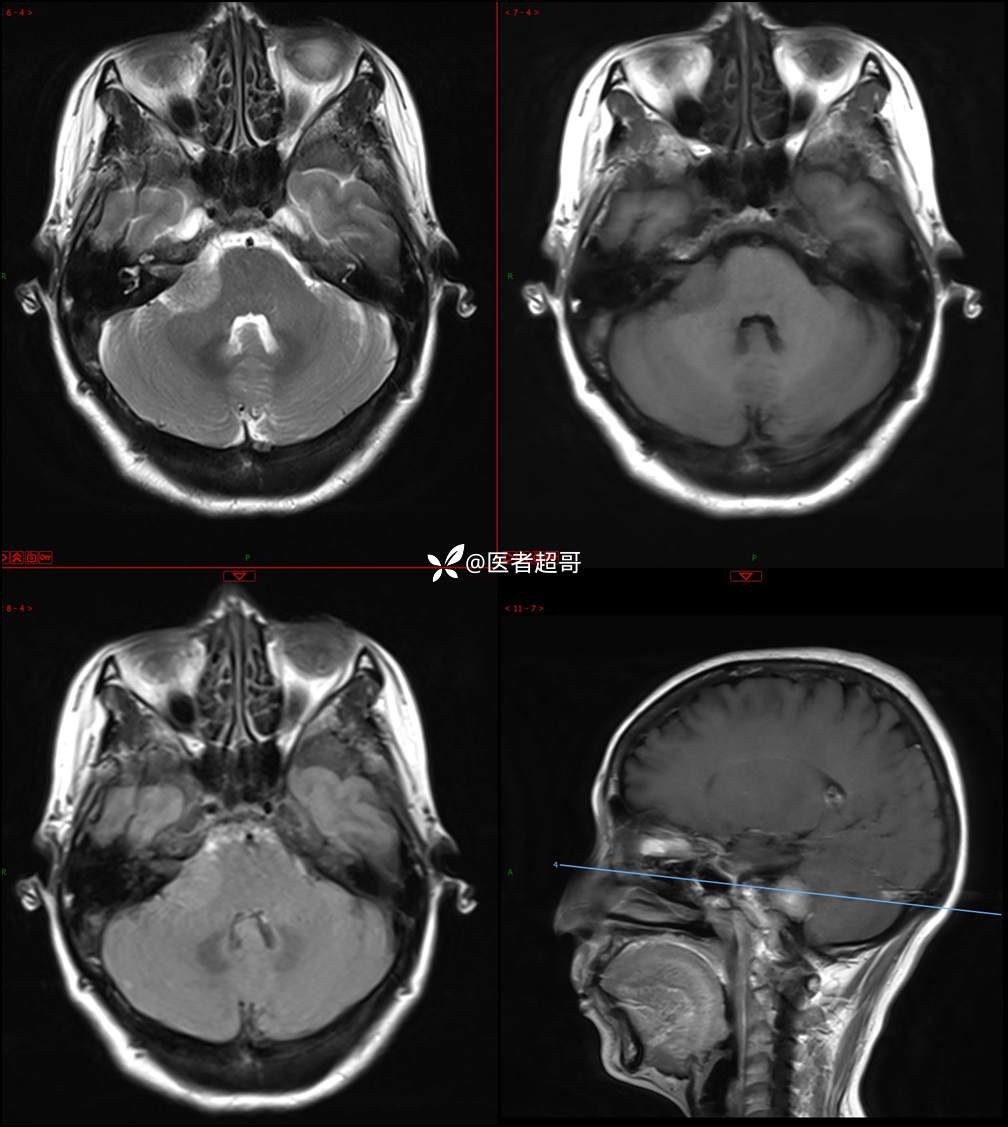

CPA区占位,是鞘瘤?脑膜瘤?请赏析!

主 诉:耳鸣3年,头晕伴恶心4天。

现病史:患者3年前出现耳鸣,蝉鸣音,反复发作,夜间自觉明显,于2018年8月至我院耳鼻喉科就诊,行颅脑CT检查未发现明显异常改变,给予对症处理(具体不详);4天前突发头晕,伴明显恶心,至市人民医院就诊,行颅脑CT未见明显异常,颅脑MRI发现右侧桥脑小脑角区占位性病变。本次发病来无明显头痛,无肢体抽动,无大小便失禁。为求进一步诊治,遂来我院门诊,以“听神经良性肿瘤”收住入院。发病来,患者神志清,精神可,二便正常,饮食可,睡眠不佳,近期体重无明显变化,否认癫痫发作病史。